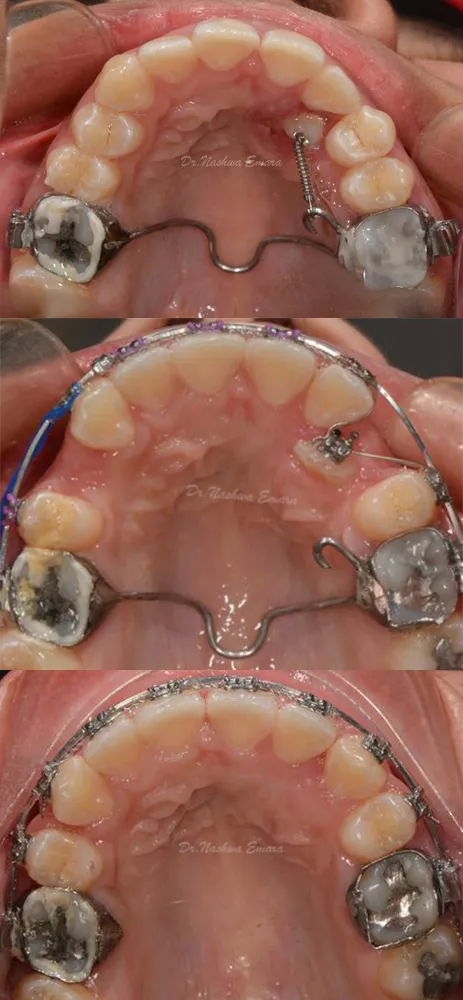

Orthodontics